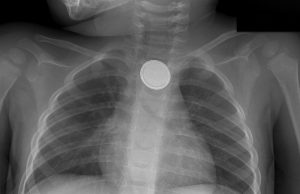

Extraen médicos monedas, uvas y figuritas de plástico del estomago de...

Ingesta de cuerpos extraños y sustancias cáusticas pueden causar consecuencias fatales si no se atienden a tiempo y debidamente, advierten especialistas